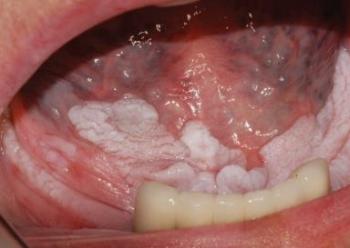

Krónikus hyperplasiás candidiasis

Ebben az esetben a fehér folt letörölhető és alatta pontszerűen vérző erythemás területeket találunk (10.13. ábra)

10.13. ábra. Candidiasis a palatumon

(Gera I. felvétele)